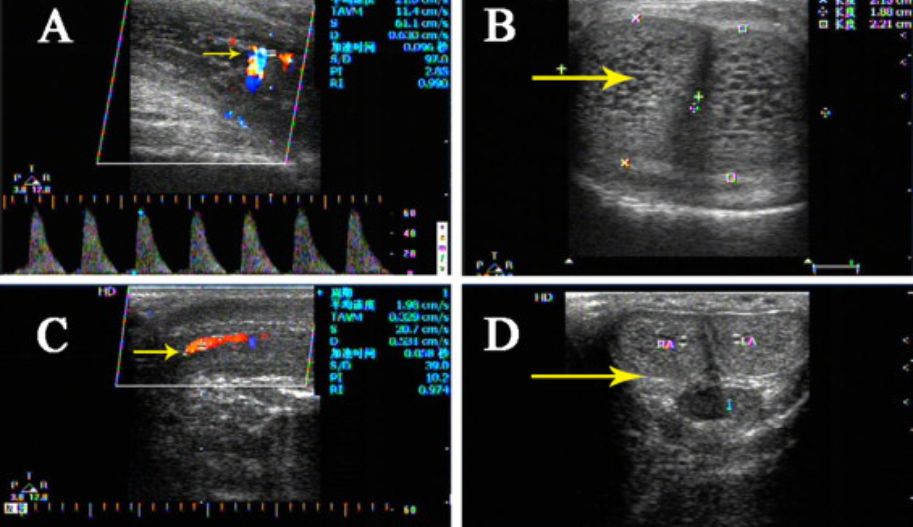

Color Doppler ultrasound provides the simultaneous visualization of blood flow while assessing the penile anatomy, plaques, fibrosis, tunica albuginea defects, masses, and fluid collections. It allows the evaluation of blood flow speed and direction.

Commonly used hemodynamic parameters include peak systolic velocity (PSV), end-diastolic velocity (EDV), and resistance index (RI).

Through the evaluation of Doppler ultrasound parameters, the vascular response can be classified as normal or pathological (indicating arterial or venous insufficiency). A PSV of 35 cm/s or greater indicates arterial sufficiency. For venous sufficiency, EDV below 5 cm/s and RI greater than 0.8 are required.